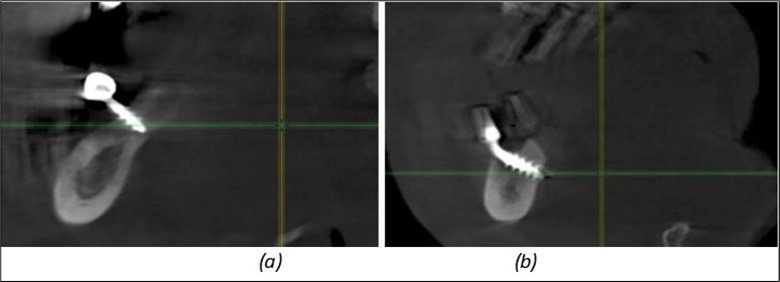

Figure 9.Implants in the pterygoid plateau area: (a) TPG implant fixed in the maxillary-sphenoid junction area, quadrant 1; (b) TPG implant fixed in the maxillary-sphenoid junction area, quadrant 2.

Implants in the pterygoid plateau area: (a) TPG implant fixed in the maxillary-sphenoid junction area, quadrant 1; (b) TPG implant fixed in the maxillary-sphenoid junction area, quadrant 2.